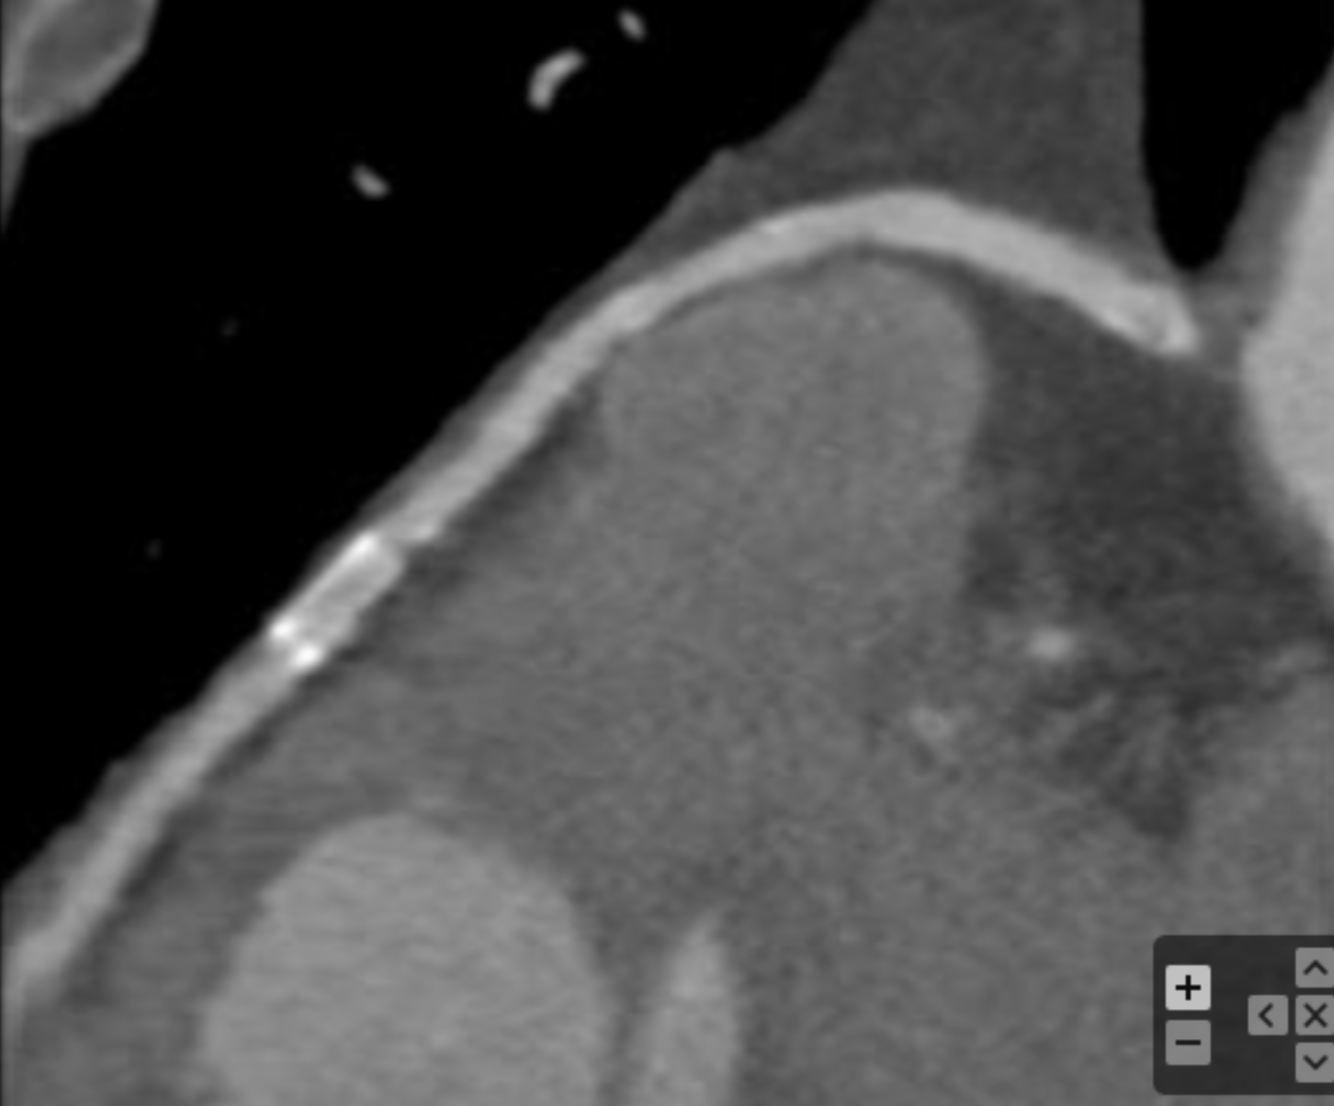

What is the arrow pointing at?

RV pacemaker leads - metal artifacts